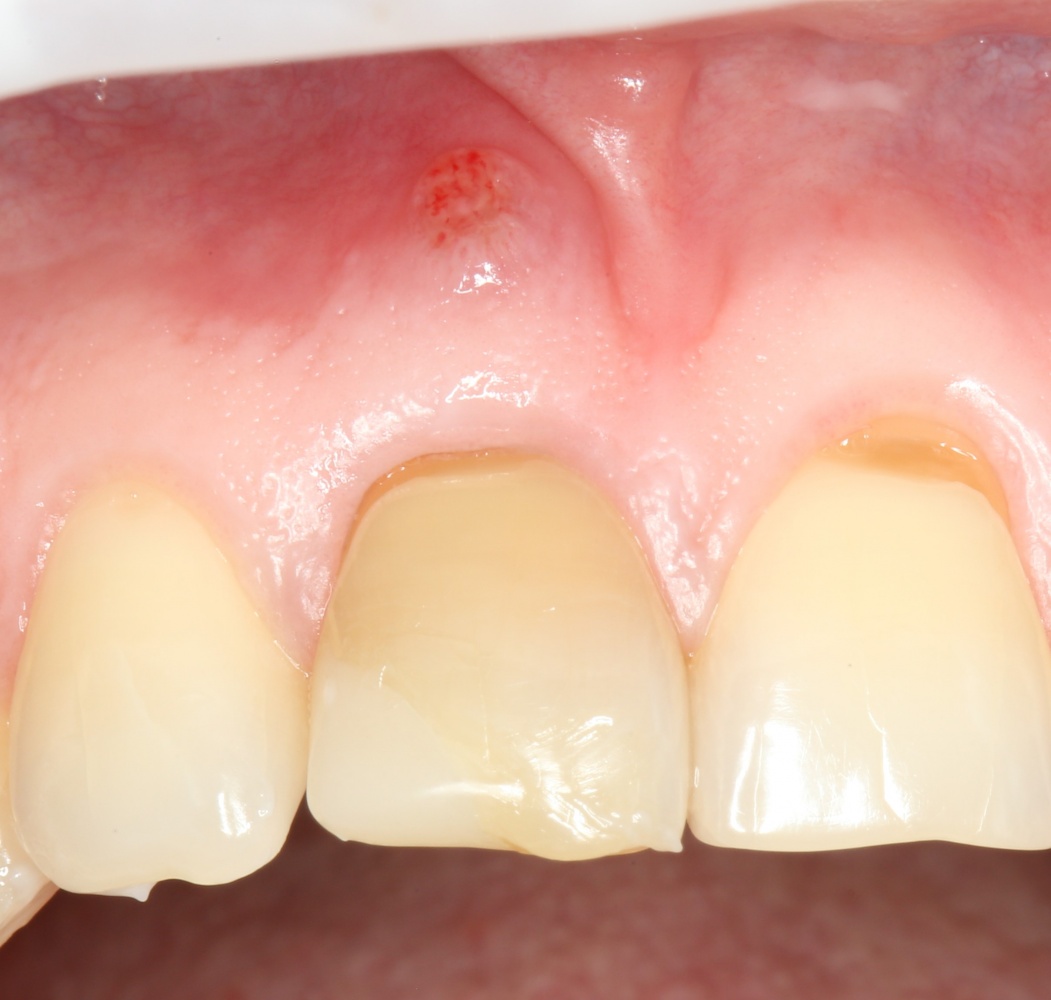

Все началось с воспаления, свищевого хода и удаления зуба:

Затем, мы готовим лунку и проверяем позиционирование импланта:

После чего аугментируем лунку. Для упаковки Bio-Oss Collagen очень удобно использовать аналоги имплантов:

Устанавливаем имплантат XiVE (Dentsply Implants):

Сразу на имплантат — временная коронка:

которая через три месяца, к моменту интеграции импланта, выглядит совсем иначе:

Ну и… к моменту установки постоянной коронки, у нас сохранился естественный контур прилегающей десны.